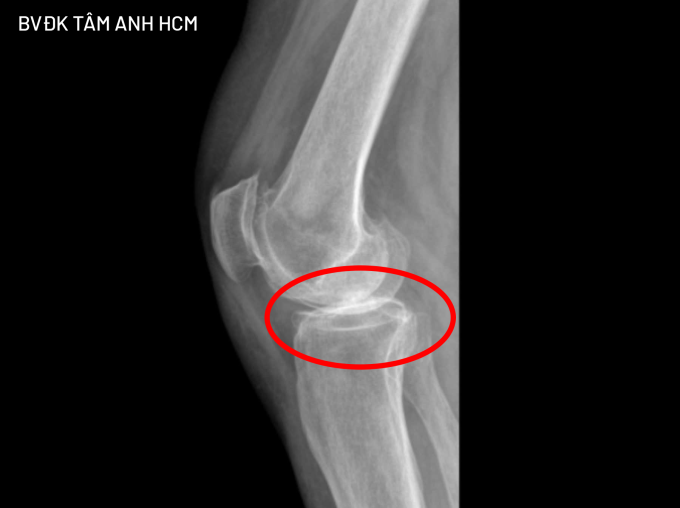

Hình X-quang cho thấy sụn khớp gối của bà Victoria gần như không còn, hai đầu xương ma sát vào nhau. Ảnh: Bệnh viện cung cấp

Bác sĩ ở Mỹ chưa chỉ định mổ, tuy nhiên do đau nhiều bà Victoria được người quen giới thiệu sang Việt Nam đến Bệnh viện Đa khoa Tâm Anh TP HCM điều trị. ThS.BS.CKI Đặng Khoa Học, Trưởng khoa Chấn thương Chỉnh hình Tổng quát, chẩn đoán bà Victoria bị thoái hóa khớp gối mạn tính giai đoạn 4 - giai đoạn nghiêm trọng nhất của bệnh. Sụn khớp gần như không còn nguyên vẹn, các đầu xương chạm trực tiếp vào nhau và dịch viêm do thoái hóa gây đau và cứng khớp.